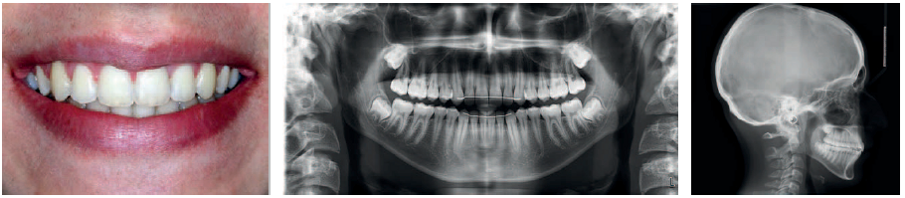

VISIT NO 5: 21 MONTHS

Seven months later, the family returned to the office over the summer break.

A long appointment was scheduled to—if all went well—remove the appliances and put a retainer in place. The day of the visit, the decision was made to proceed.

When I announced that the treatment would be completed that day, the patient and his parents had quite a memorable reaction: “Already? It went so fast! Thank you! He is going to have the best summer break!”

The results, although not perfect, were remarkable. The end-of-treatment records clearly show good tissue quality (periodontal and root integrity), undoubtedly thanks to the use of minimal force with long rest periods, a minimal number of archwires, and bonding which allowed for continuous improvement throughout the entire treatment, from beginning to end.

That same day, we began treatment for the youngest sibling, using the same protocol.

VISIT NO 6: POST-RETENTION PHOTOS +12 MONTHS